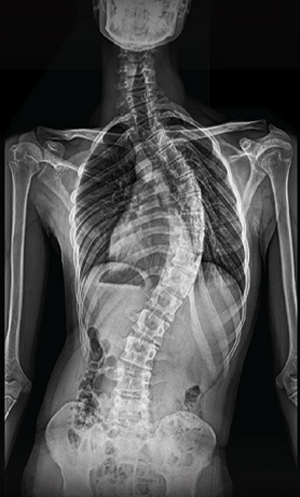

Scoliosis is a common condition characterized by a sideways curvature of the spine, often emerging during puberty. While its origins can vary, most cases are mild. However, without proper attention, severe deformities may lead to significant functional disabilities, impacting lung function and overall well-being.

Gallery : Before - After

After

Before